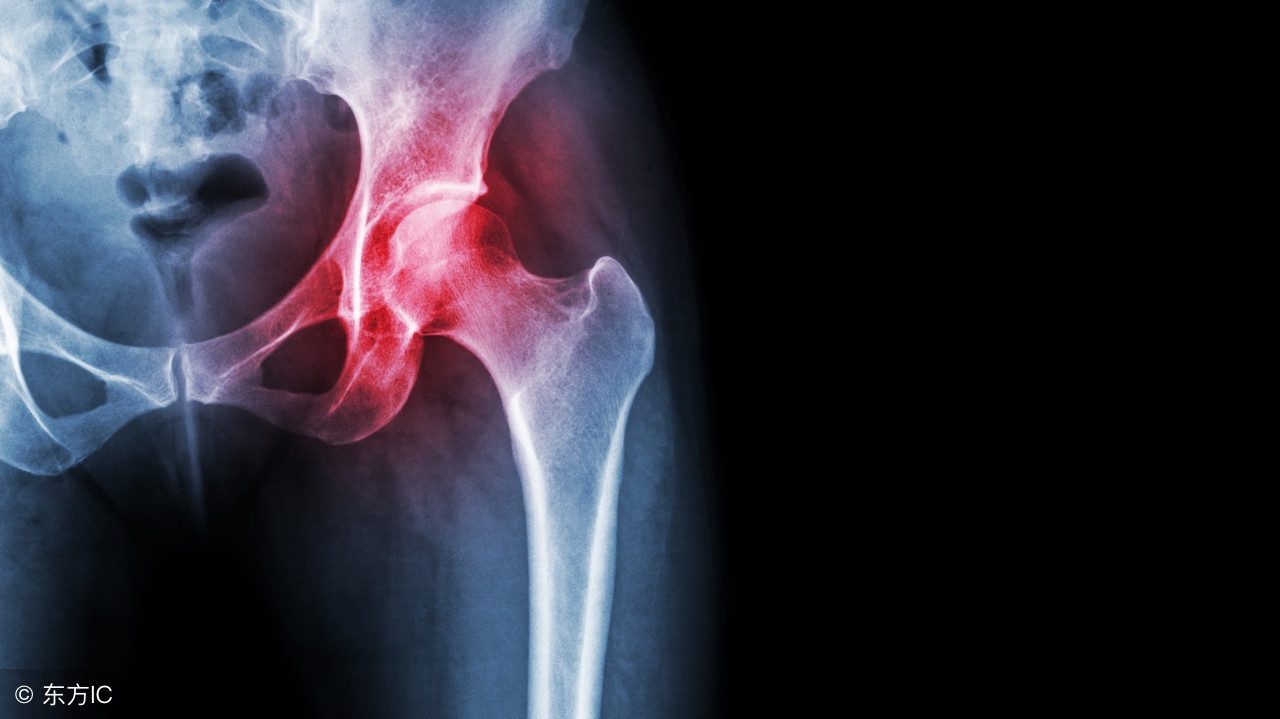

股骨头坏死